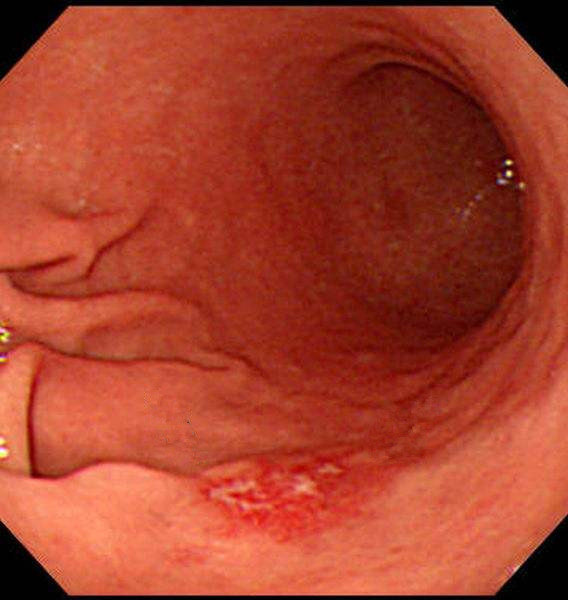

萎縮性慢性胃炎